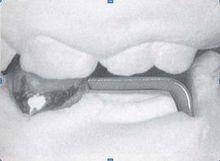

帶環絲圈式間隙保持器

咬合誘導2. 絲圈式保持器

適應證:

· 單側第一乳磨牙喪失

· 第一恆磨牙萌出後第二乳磨牙喪失

· 雙側乳磨牙早失